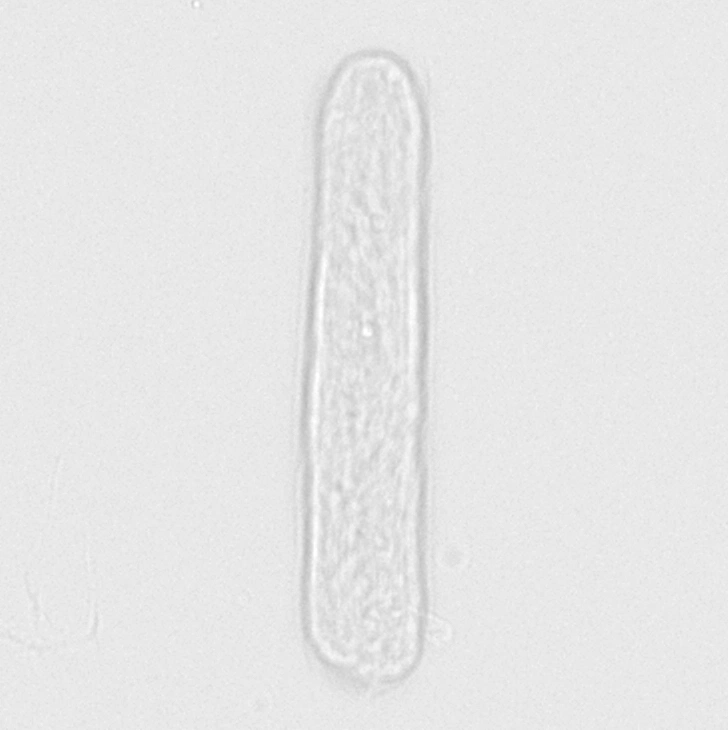

Модуль производит подсчёт частиц, используя для этого метод проточной плоскостной (ламинарной) цитометрии с цифровой визуализацией и идентификацией c помощью нейросети (DeepCNN).

Точная автоматическая классификация форменных элементов мочи с уровнем соответствия микроскопии >95%.